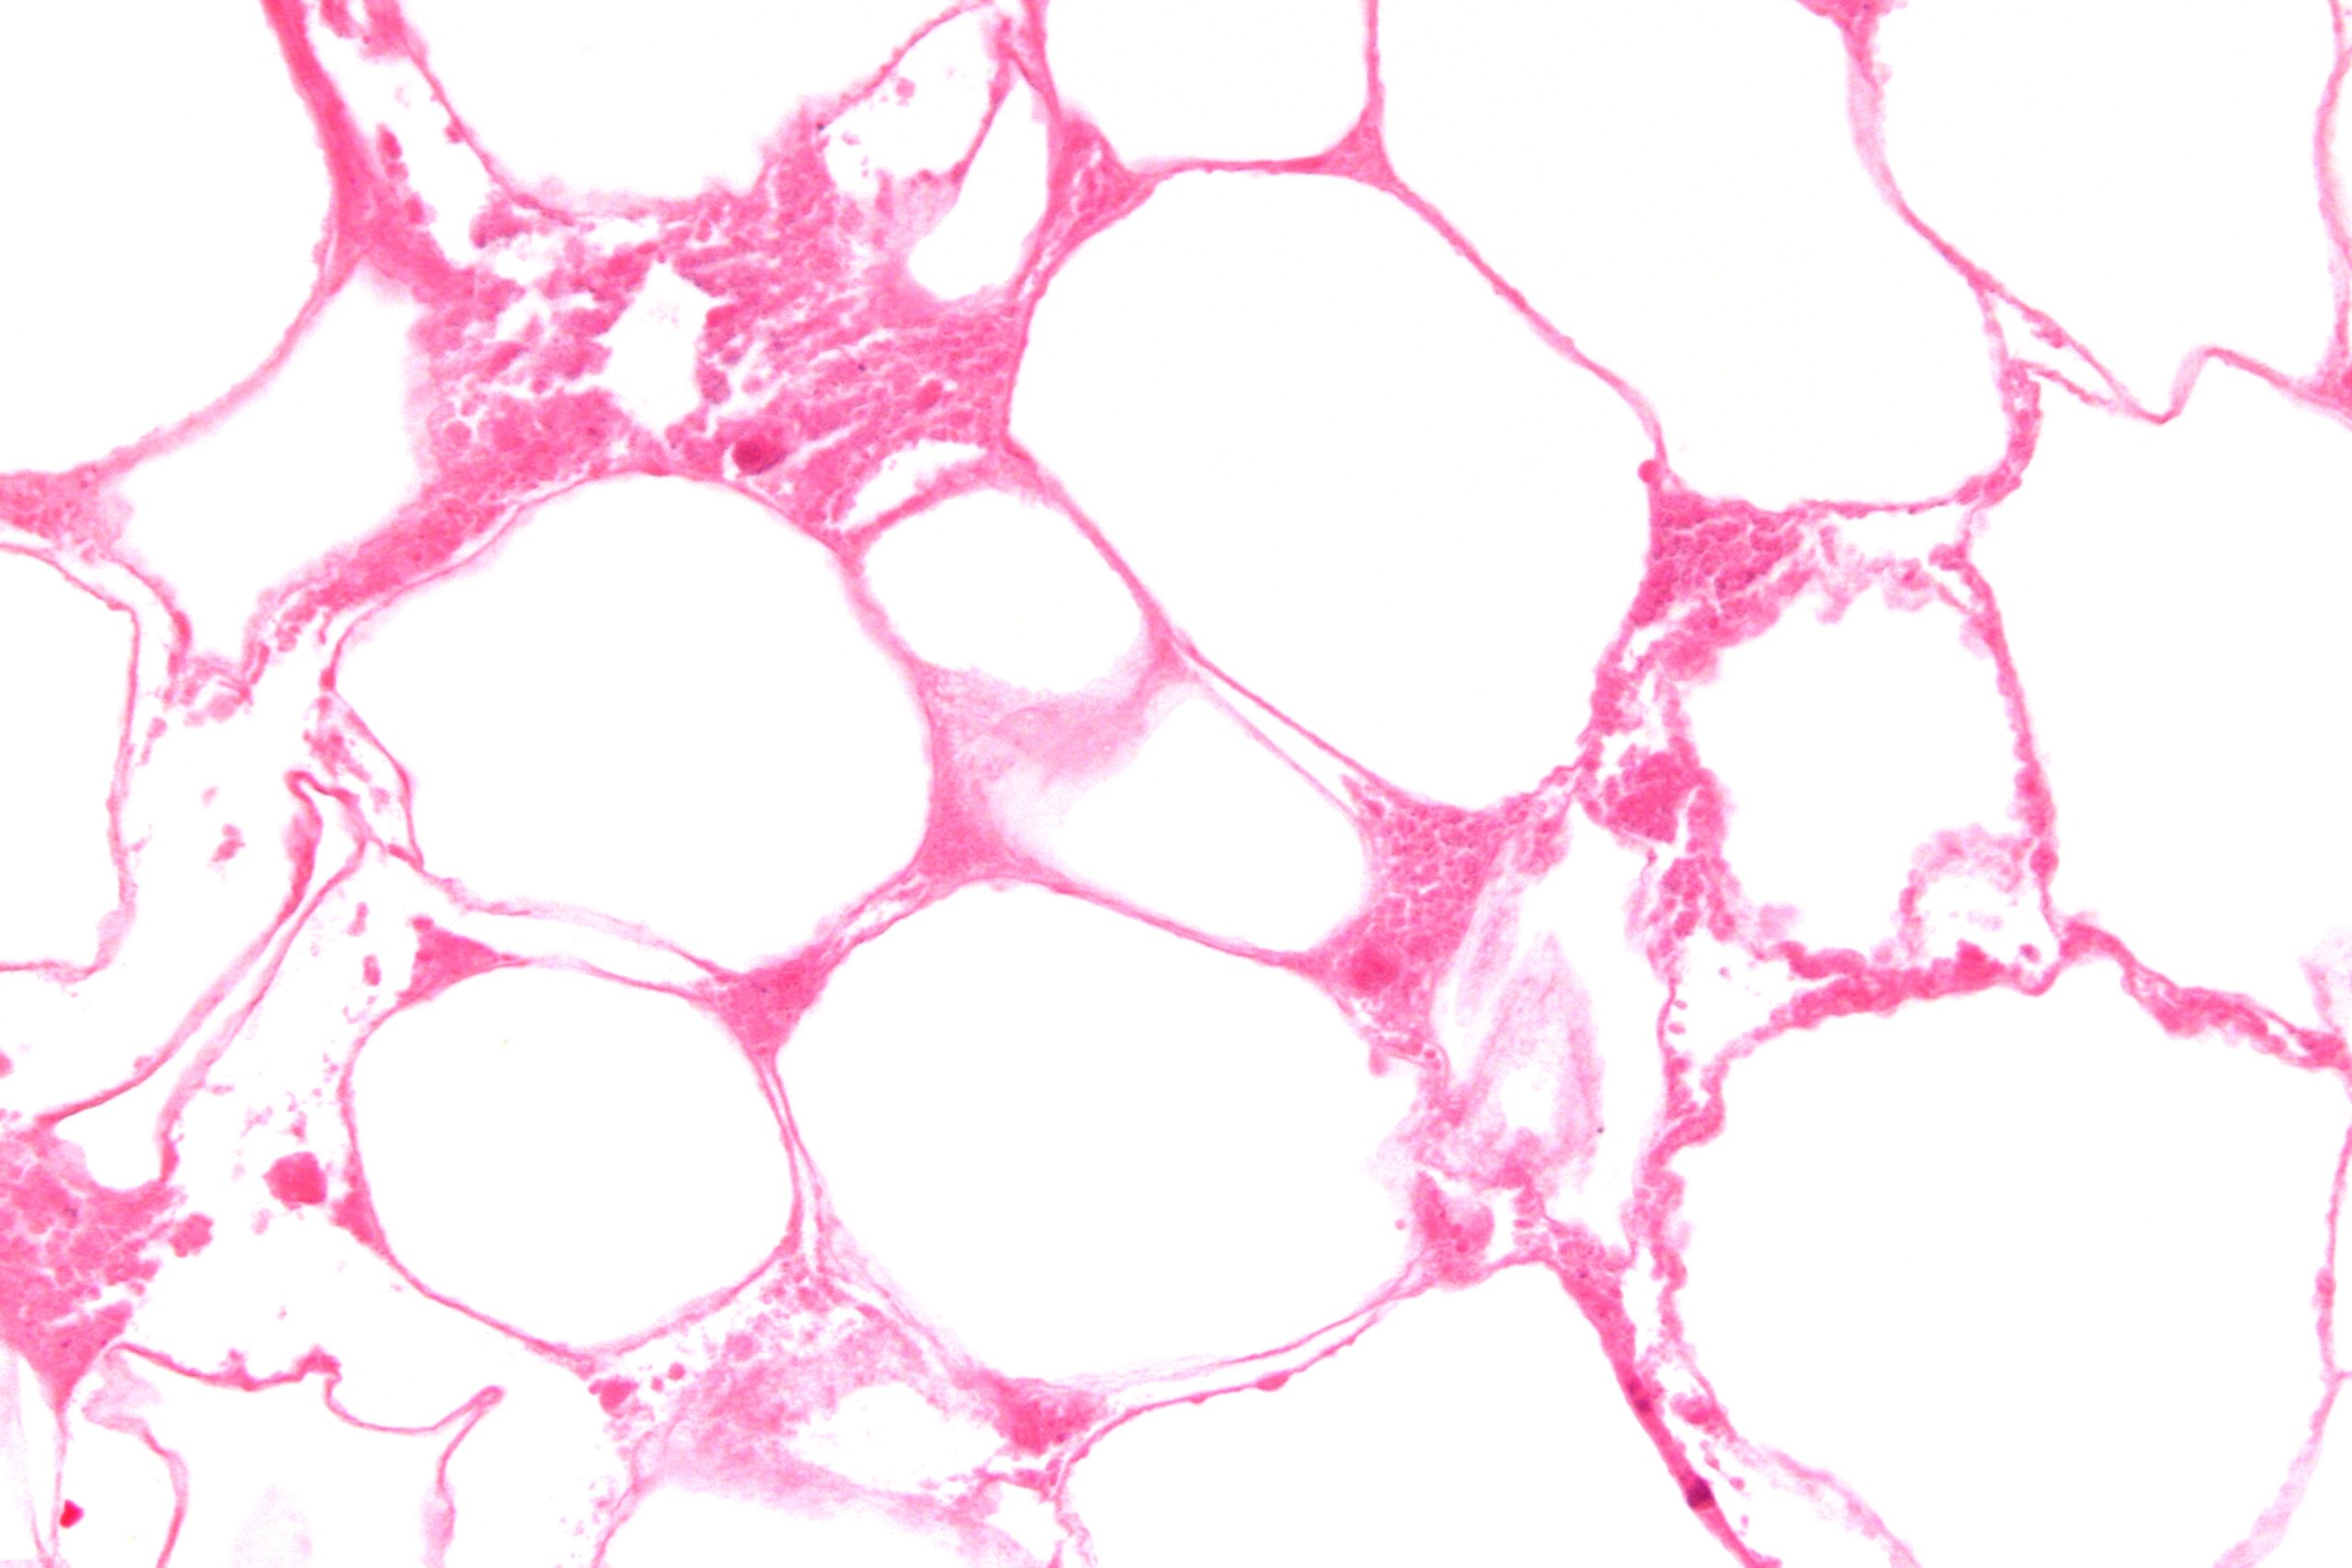

Chapter 1 Introduction to Pathophysiology; Cellular Responses to Stress, Injury, and Aging